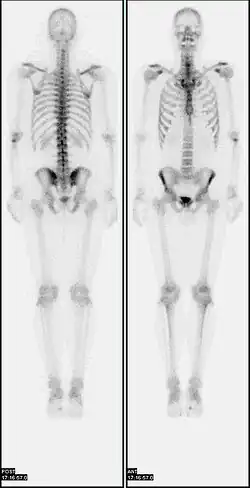

Nuclear medicine (nuclear radiology)[1] is a medical specialty involving the application of radioactive substances in the diagnosis and treatment of disease. Nuclear imaging is, in a sense, radiology done inside out, because it records radiation emitted from within the body rather than radiation that is transmitted through the body from external sources like X-ray generators. In addition, nuclear medicine scans differ from radiology, as the emphasis is not on imaging anatomy, but on the function. For this reason, it is called a physiological imaging modality. Single photon emission computed tomography (SPECT) and positron emission tomography (PET) scans are the two most common imaging modalities in nuclear medicine.[2]